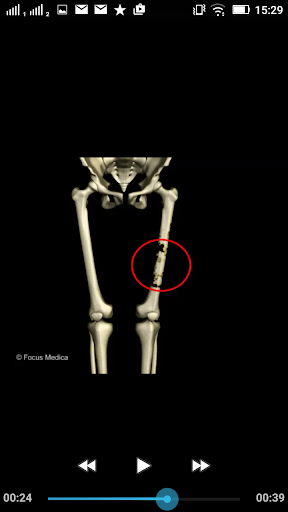

The FOCUS Animated Pocket Dictionary of RHEUMATOLOGY is the first ever animated dictionary in the subject. A valuable reference for physicians and students alike, it covers 100 rheumatology related terms and definitions. All the definitions have been graphically described with the help of 3D animations and are accompanied by text definitions.

The Focus Animated Pocket Dictionaries are the world’s first ever animated dictionaries that provide definitions of medical terms with the aid of realistic and narrated 3D animations, complimented with text definitions. Terms arranged alphabetically making definitions easy to search. These unique visual dictionaries are excellent reference sources for health professionals, students and health consumers. The videos play independent of the internet once downloaded.